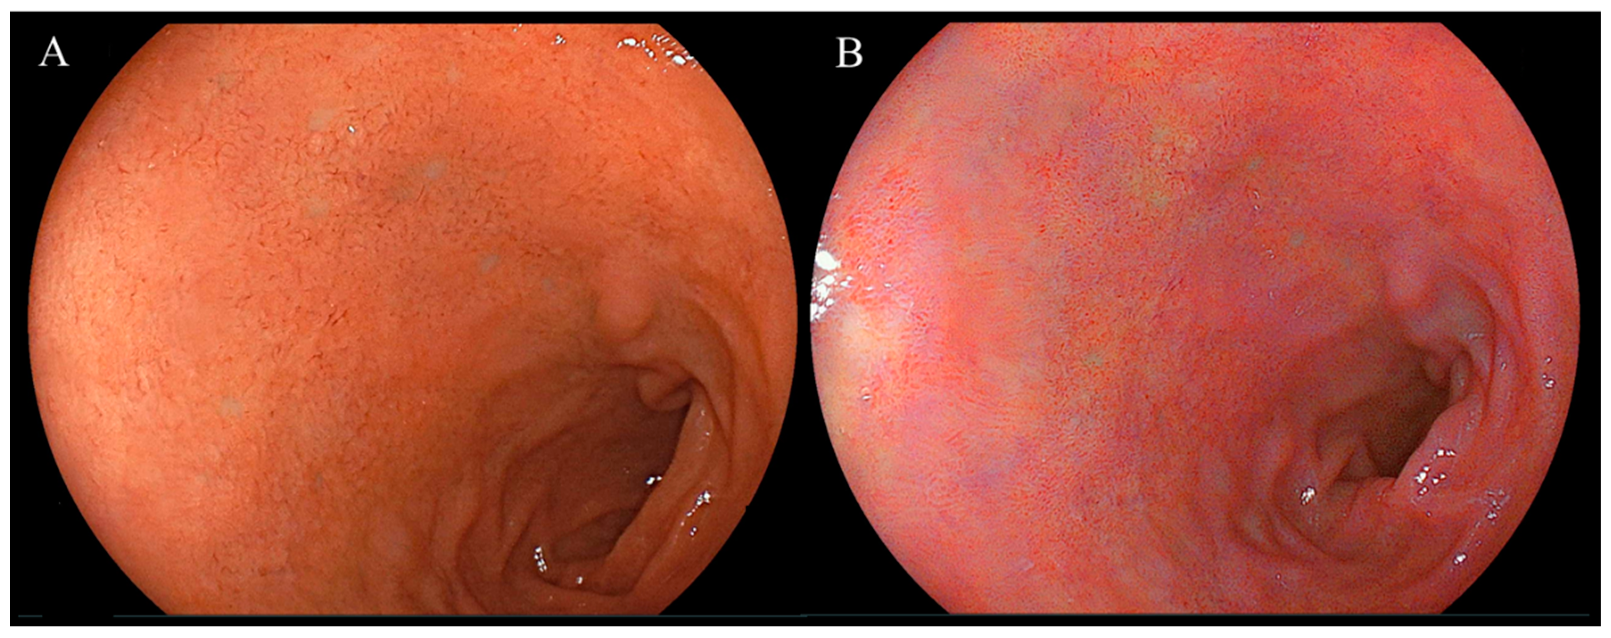

Endoscopic images taken in the duodenal mucosa of bulbs, with or without red mucosa, are shown in Figure 2 and Figure 3, respectively. Approximately 21 out of 302 (7.0%) cases were in the redness (+) group and the concordance rate between the two assessors was 86.4% (261/302). Figure 4 presents endoscopic images after the use of WLI and LCI with ROIs. An analysis of L* a* b* color values for the duodenal bulb was carried out (Table 3). White light imaging and LCI showed significant differences between the L* a* b* color values. The red component (a*) of the duodenal bulb with LCI was significantly higher than that using WLI in the redness (+) group but was found to be significantly lower in the redness (−) group. Comparing the L* a* b* color values between redness (+) and (−) groups, the a* values were significantly higher in the redness (+) group for both WLI and LCI (p < 0.001). However, a difference was not observed in b* values with LCI (WLI: p = 0.021, LCI: p = 0.338). Subjective evaluation showed that the redness (+) group consisted of 7% of 302 cases. Objective evaluation showed that the red component (a*) of the duodenal bulb with LCI was significantly higher than WLI in the redness (+) group.

Figure 3.

Representative endoscopic images of the duodenal mucosa of bulbs not showing red mucosa using white light imaging and linked color imaging. (A) White light imaging (WLI). Duodenal mucosa of bulbs. (B) Linked color imaging (LCI). The duodenal mucosa of bulbs was not visible in a red color using LCI.